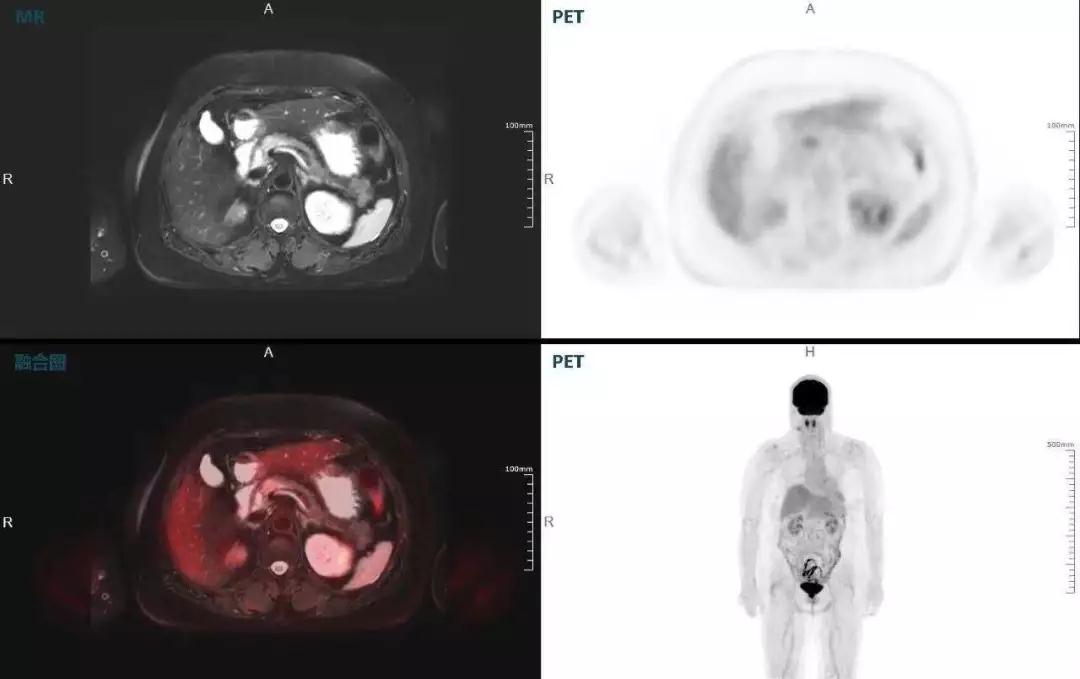

胰腺癌

中山醫(yī)院核醫(yī)學科在臨床實踐中發(fā)現,基于聯(lián)影“時空一體”超清TOF PET/MR,不僅解剖信息和代謝信息能夠完美融合呈現,同時精細展示局部病灶與周圍組織的復雜關系,并能全盤檢測病灶的全身轉移,為醫(yī)生臨床診斷提供更豐富信息。

(胰腺腫瘤,MR顯示胰腺體部信號異常,PET顯示稍高攝取,結構改變和功能異常提示胰腺MT可能大。)